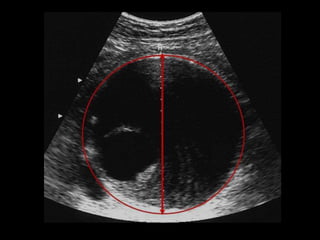

AAA, mesure du calibre

Diamètre antéro-postérieur externe (adventice-adventice) maxima

UK Small Aneurysm Trial: design, methods, progress. Eur J Vasc Endovasc Surg 1995

Orienter la coupe de

manière à avoir une

section circulaire

" AAA size is defined as the maximum external cross-sectional diameter in any

direction " .

Lederle F.A. et al. Design of the abdominal aortic Aneurysm Detection and Management

Study (ADAM Study). J Vasc Surg 1994

Moyenne

d'au moins

3 mesures

SchémaF.Becker

AAA, mesure ducalibre Diamètre antéro-postérieur externe (adventice-adventice) maxima UK Small Aneurysm Trial: design, methods, progress. Eur J Vasc Endovasc Surg 1995 Orienter la coupe de manière à avoir une section circulaire " AAA size is defined as the maximum external cross-sectional diameter in any direction " . Lederle F.A. et al. Design of the abdominal aortic Aneurysm Detection and Management Study (ADAM Study). J Vasc Surg 1994 Moyenne d'au moins 3 mesures SchémaF.Becker francois.becker@wanadoo.fr